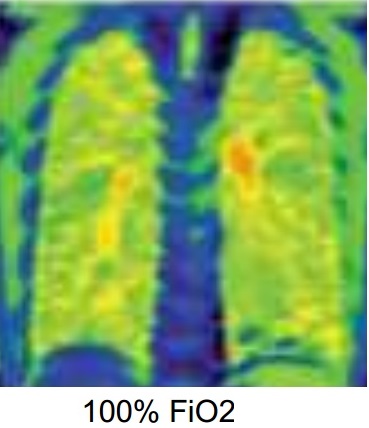

Image

radiologique IRM fonctionelle de ventilation de

oxygene normale du poumon |